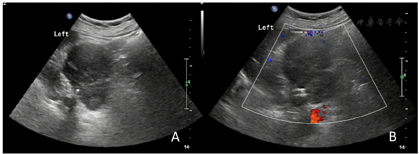

入院后完善血尿常规、大便常规及相关生化检查。肾上腺内分泌功能检查示肾素22.19 pg/ml,血管紧张素Ⅱ 241.33 pg/ml,醛固酮134.95 pg/ml,醛固酮肾素比值6.08 μg/L,皮质醇0点(CROTISOL)166.00 μg/L,皮质醇4点(CROTISOL)218.00 μg/L。胸片、心电图正常。腹部超声检查显示左侧肾上腺区可见一大小约7.6 cm×6.2 cm的低回声团,边界欠清,与左侧肾脏组织分界不清,腹腔内及腹膜后区未见明显肿大淋巴结回声。超声提示左侧肾上腺区实性占位性病变(图1)。

ACC的影像学诊断主要依靠超声、CT及MRI等检查,特别是无内分泌症状的非功能性肿瘤更需要影像学检查明确诊断。超声检查是首选初筛检查,具有无创和可重复的特点,可大致了解肿瘤一般情况、边界、内部及周边血流情况。ACC的超声典型表现为肾上腺区较大低回声占位性病灶,通常直径大于5 cm,内部回声不均匀,边界不清,形态不定,可呈圆形、椭圆形或分叶状,彩色多普勒超声示肿块内部多可探及血流信号,少数周边可见血流信号。肾上腺皮质恶性肿瘤超声声像图表现主要取决于肿瘤的大小,中等大小(3~5 cm)的皮质恶性肿瘤特征性地固定于肾上腺部位,边界清晰,偶可见包膜,内部回声均匀或不均匀[9];大于5 cm的皮质恶性肿瘤可与肝或脾紧密相贴,内部因出血坏死形成的不规则高回声团或无回声,部分病例可见强回声钙化,当较大肿瘤显示分叶状,内见"瘢痕"征,即放射状回声,则恶性可能性变大。疑为ACC的患者还应行腹膜后及腹腔淋巴结扫查,有时可见到肿大淋巴结,部分患者合并有下腔静脉及肾静脉癌栓,病灶可见出血及坏死区,少数可有钙化,癌症容易侵犯肾上腺静脉、下腔静脉,可发生肝,脑,骨转移。CT对于鉴别肿瘤良恶性、确定肿瘤分期及手术方式有重要作用。皮质癌的CT特征性表现为轮廓不规则,密度不均,假包膜形成,中央区沙粒样钙化,内部出血坏死,增强扫描时动脉期不均匀强化,延迟期渐进式持续强化[3]。Xiao等[10]报道CT对于诊断ACC敏感性高达98%,误诊率及漏诊率小于10%。同时CT对于确定肿瘤有无外生性生长,是否淋巴结转移及周围脏器浸润情况有重要意义。